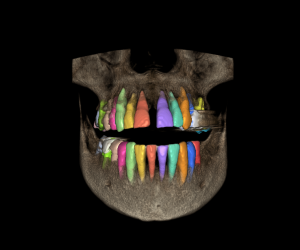

Curso Exoplan BASIC

Carga de la ficha y base de datos (DentalDB)

Manejo del software / Herramientas

Planificación

Guide creator

Curso Exoplan PRO

Curso Exoplan BASIC (Incluido)

Técnica Doble Dicom

Técnica Dicom Stl

Curso Flujo Exocad / Exoplan

Curso integración avanzado para dentistas (incluido)

Curso Exoplan PRO (incluido)

Dirigido a Dentistas los cuales quieran realizar la planificación y diseño del encerado, colocación de implantes Full Mouth y carga inmediata o diferida.